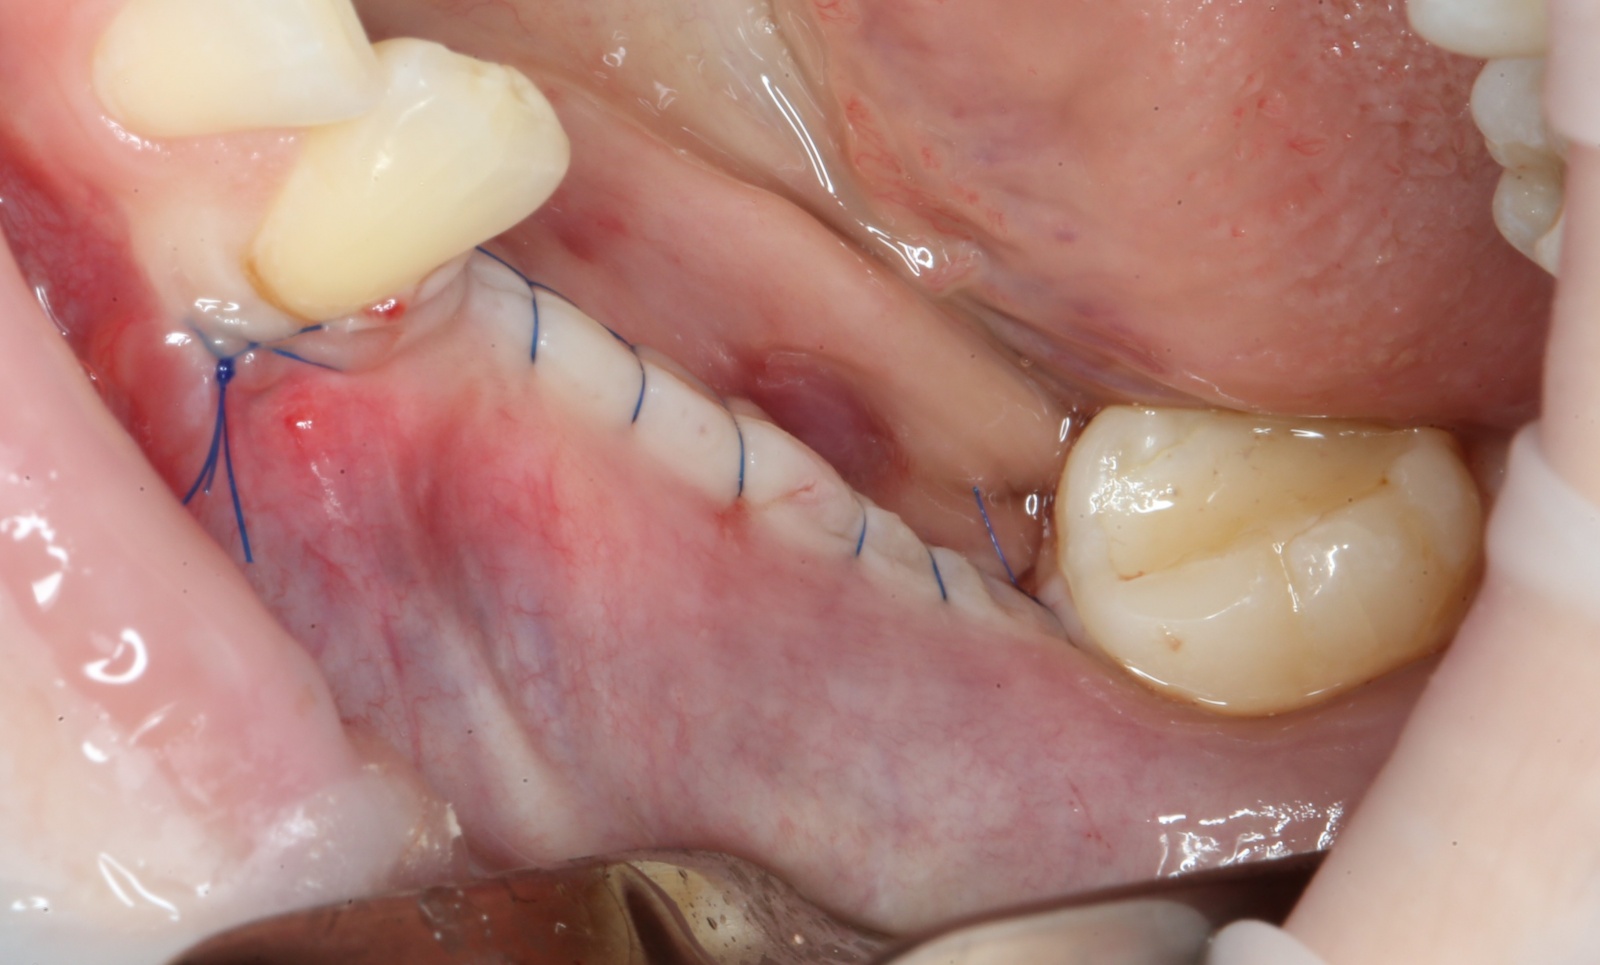

Операция закончена:

Операция, классически, заканчивается наложением швов: